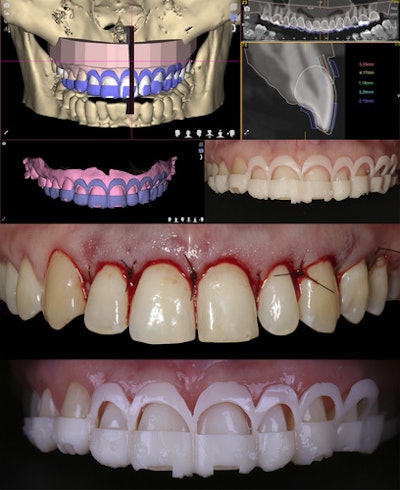

The patient's cone-beam computed tomography scan files were matched to intraoral scan files. Surgical planning was transferred to a digital surgical guide, which allowed clinicians to assess the relationship between periodontal and dental tissue in cross-sectional views, the authors wrote.

Based on the measurements of gingival and bone tissue with the anterior teeth, a crown lengthening guide was designed and printed to guide resection.

After a two-month healing period, photos and an intraoral scan were taken to analyze the patient's periodontal condition and begin restorative treatment. Based on the previous digital wax-up, shells were printed and tried on.

Restoration began by manufacturing resin guides to orient teeth preparation. The initial digital wax-up was used as a reference, and preparation guides were designed and printed, according to the report.

Clinicians performed tooth reduction according to the first preparation guide. Using additional guides, labial and incisal reduction were performed. The monolithic CAD/CAM restorations, which were designed and milled using a lithium disilicate material, provided a natural appearance.

After tooth preparation, the mouth was scanned, and the tooth shade was selected. To guide the restorations, the digital models were superimposed onto the digital wax-up. Then, the final restorations were completed. In the end, the similarities between the wax-up, the mock-up, the designed restorations, and the final restorations could be seen, the authors wrote.